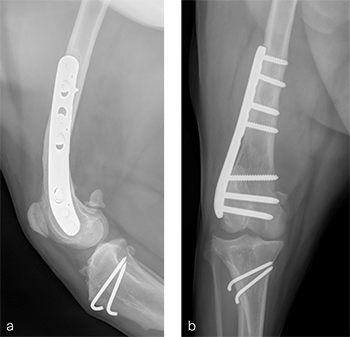

A routine lateral approach to the distal femur and stifle joint was performed. Results of the cruciate ligaments examination were normal. The lateral joint capsule was dissected to expose the distal femoral condyle. An alignment jig was placed in a craniocaudal direction to ensure that deformity correction was limited to the frontal plane. A 12 lateral closing wedge ostectomy was performed and the femoral condyle was reduced and temporarily stabilized with divergent K-wires. A 7-hole left 3.5 LCP DFO plate was placed on the lateral femur and secured with a combination of 3.5 mm cortex and locking screws. The compression function of the plate was used to compress the ends of the two bone segments. Temporary K-wires were removed and a wedge sulcoplasty was performed to deepen the trochlear groove for improved patella articulation. A tibial tuberosity transposition was performed and stabilized with two pins and tension band wire. Routine closure was performed. Total surgical time was 1 hour and 45 minutes. Postoperative x-rays demonstrate the position of a left, 7-hole, 3.5 LCP DFO plate and associated tibial tuberosity transposition. In the medioateral view it can be appreciated that plate contour matches the normal distal femoral procurvatum and screws are positioned caudally away from the trochlea (Fig 6a). This allows for an unimpeded sulcoplasty while maximizing screw purchase caudally. The compression applied with the plate has resulted in excellent apposition. The patella is visible within the trochlear groove. In the craniocaudal view the plate contour matches the anatomical contour of the distal femoral condyle (Fig 6b). The anatomical Lateral Distal Femoral Angle is reduced to 92. During the follow up after 8 weeks, clinical signs have resolved, limb use is excellent, and stifle joint range of motion is normal without evidence of pain. In the mediolateral x-ray the osteotomy has healed (Fig 7a). Plate and screw position remain unchanged. The tibial tuberosity transposition is healing, and implants remain unchanged. The patella remains reduced within the trochlear groove. In the craniocaudal view the osteotomy has healed and is no longer visible (Fig 7b). Implants are stable and the patella is tracking normally.